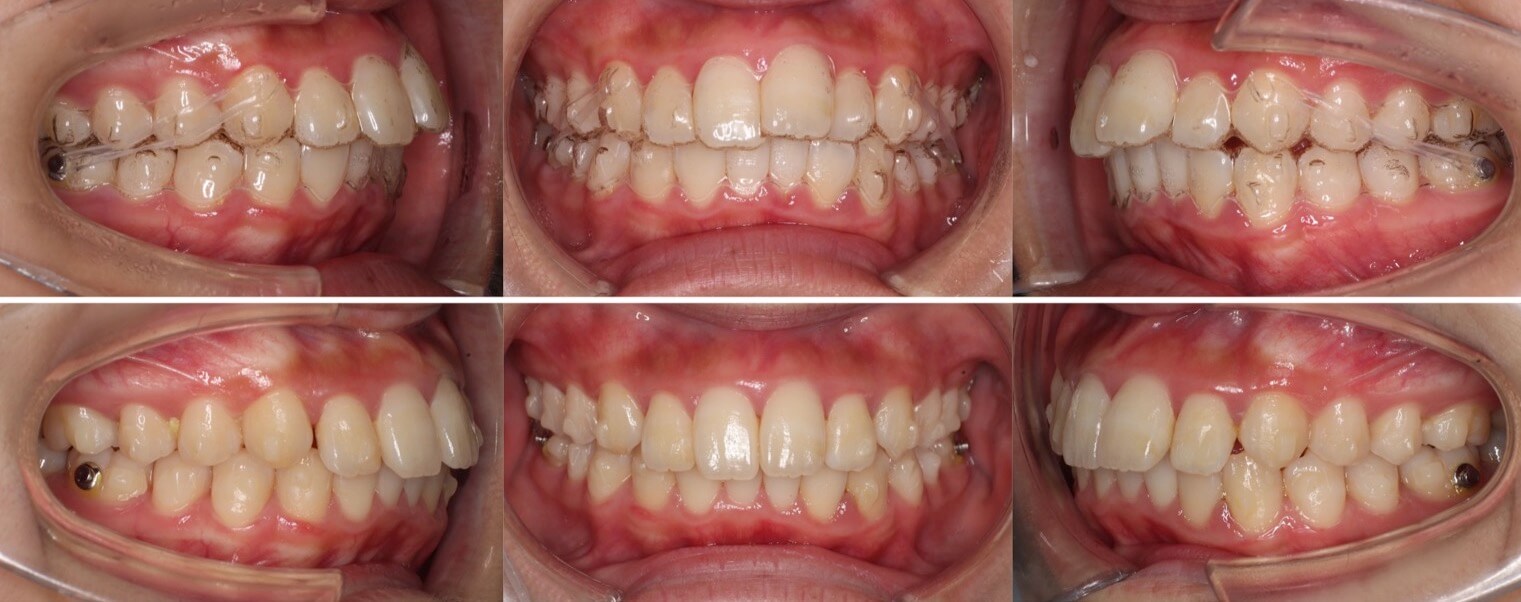

高校生女性・唇側矯正・上下抜歯

<症例概要> 難易度:★★★☆☆

主訴:前歯と口元の突出

年齢・性別:高校生女性

住まい:千葉県佐倉市

症状:下顎後退・上顎前歯唇側傾斜

治療方針:抜歯空隙の閉鎖(中等度固定)

治療装置:唇側矯正装置

固定:ナンスホールディングアーチ

抜歯:上第一小臼歯・下第二小臼歯(計4本)

治療期間:2年4か月

リテーナー:上下プレートタイプ+フィックスタイプ

治療費用:968,000(税込)

代表的副作用:痛み・治療後の後戻り・歯根吸収・歯髄壊死・歯肉退縮

▶︎その他の副作用

前歯が出ているため、口元が突出し口が閉じにくいという状態でした。上の前歯の突出が強いため、下の抜歯部位は第二小臼歯を選択し、前歯の後方移動量を調整しました。治療後はすっきりとした横顔になりました。